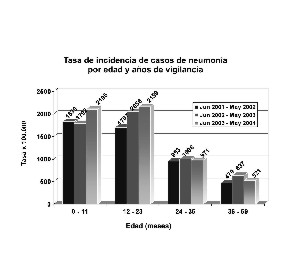

De 2.184 pacientes captados, se dispuso para el análisis de 93,1% de las historias clínicas y las fotografías digitales. Según la interpretación radiográfica, 826 (40,6%) fueron neumonías consolidantes, 941 (46,3%) neumonías no consolidantes y 267 no fueron neumonías (13,1%). Los niños menores de dos años de edad predominaron (66,9%), de los cuales 45,8% tuvieron neumonías consolidantes. La tasa de incidencia anual de neumonía consolidante en los niños hospitalizados menores de cinco años fue 1.152 x 105, pero las tasas más altas se registraron en los pacientes menores de dos años.